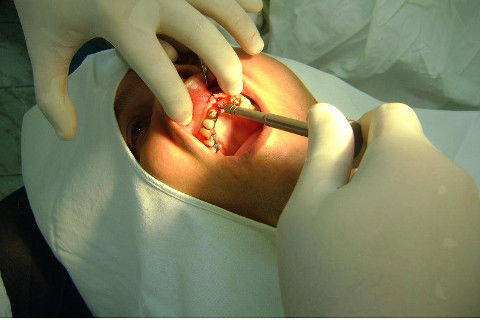

Cirurgia realizada hoje de manhã...No planejamento percebi medindo espessura do rebordo com especímetro que as medidas não estavam muito boas, ou o ideal, em torno de 4,5 a 5 mm ate´o terço médio do rebordo e melhorava no final, com 6 a 7 mm. Optei então por uma pequena expansão usando os expansores rosqueáveis. Aconteceu uma pequena fenestração na hora da fixação dos implantes, especialmente na região do 22 que fraturou o início da tábua óssea, mas não me preocupei porque não foi mais do que 2 mm de fratura em direção apical, o implante ficou infraósseo e com boa estabilidade (60 N no 21 e 40 N no 22). Esta fratura tb não deixou osso completamente solto, foi do tipo galho verde, deixei em posição e suturei normalmente. Só não fiz e nem estava planejado carga imediata mesmo, mais pelo motivo da oclusão inadequada do caso.

Fotos do caso